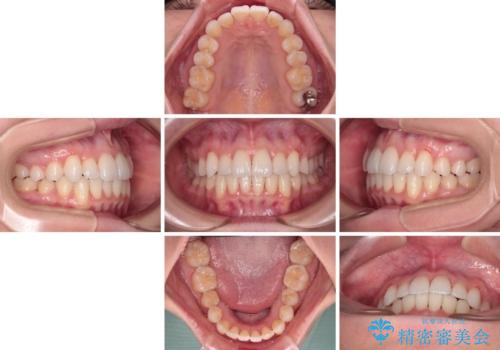

- 上下前歯のデコボコ、特に右上の八重歯を気にして来院された患者様です。

妊娠、出産の予定があり、毎月の通院が困難となる可能性があったため、インビザラインによる矯正治療を行うこととしました。

事前に親知らずを抜歯しておき、出産時期に困ることのないように準備をした上で治療を開始しました。